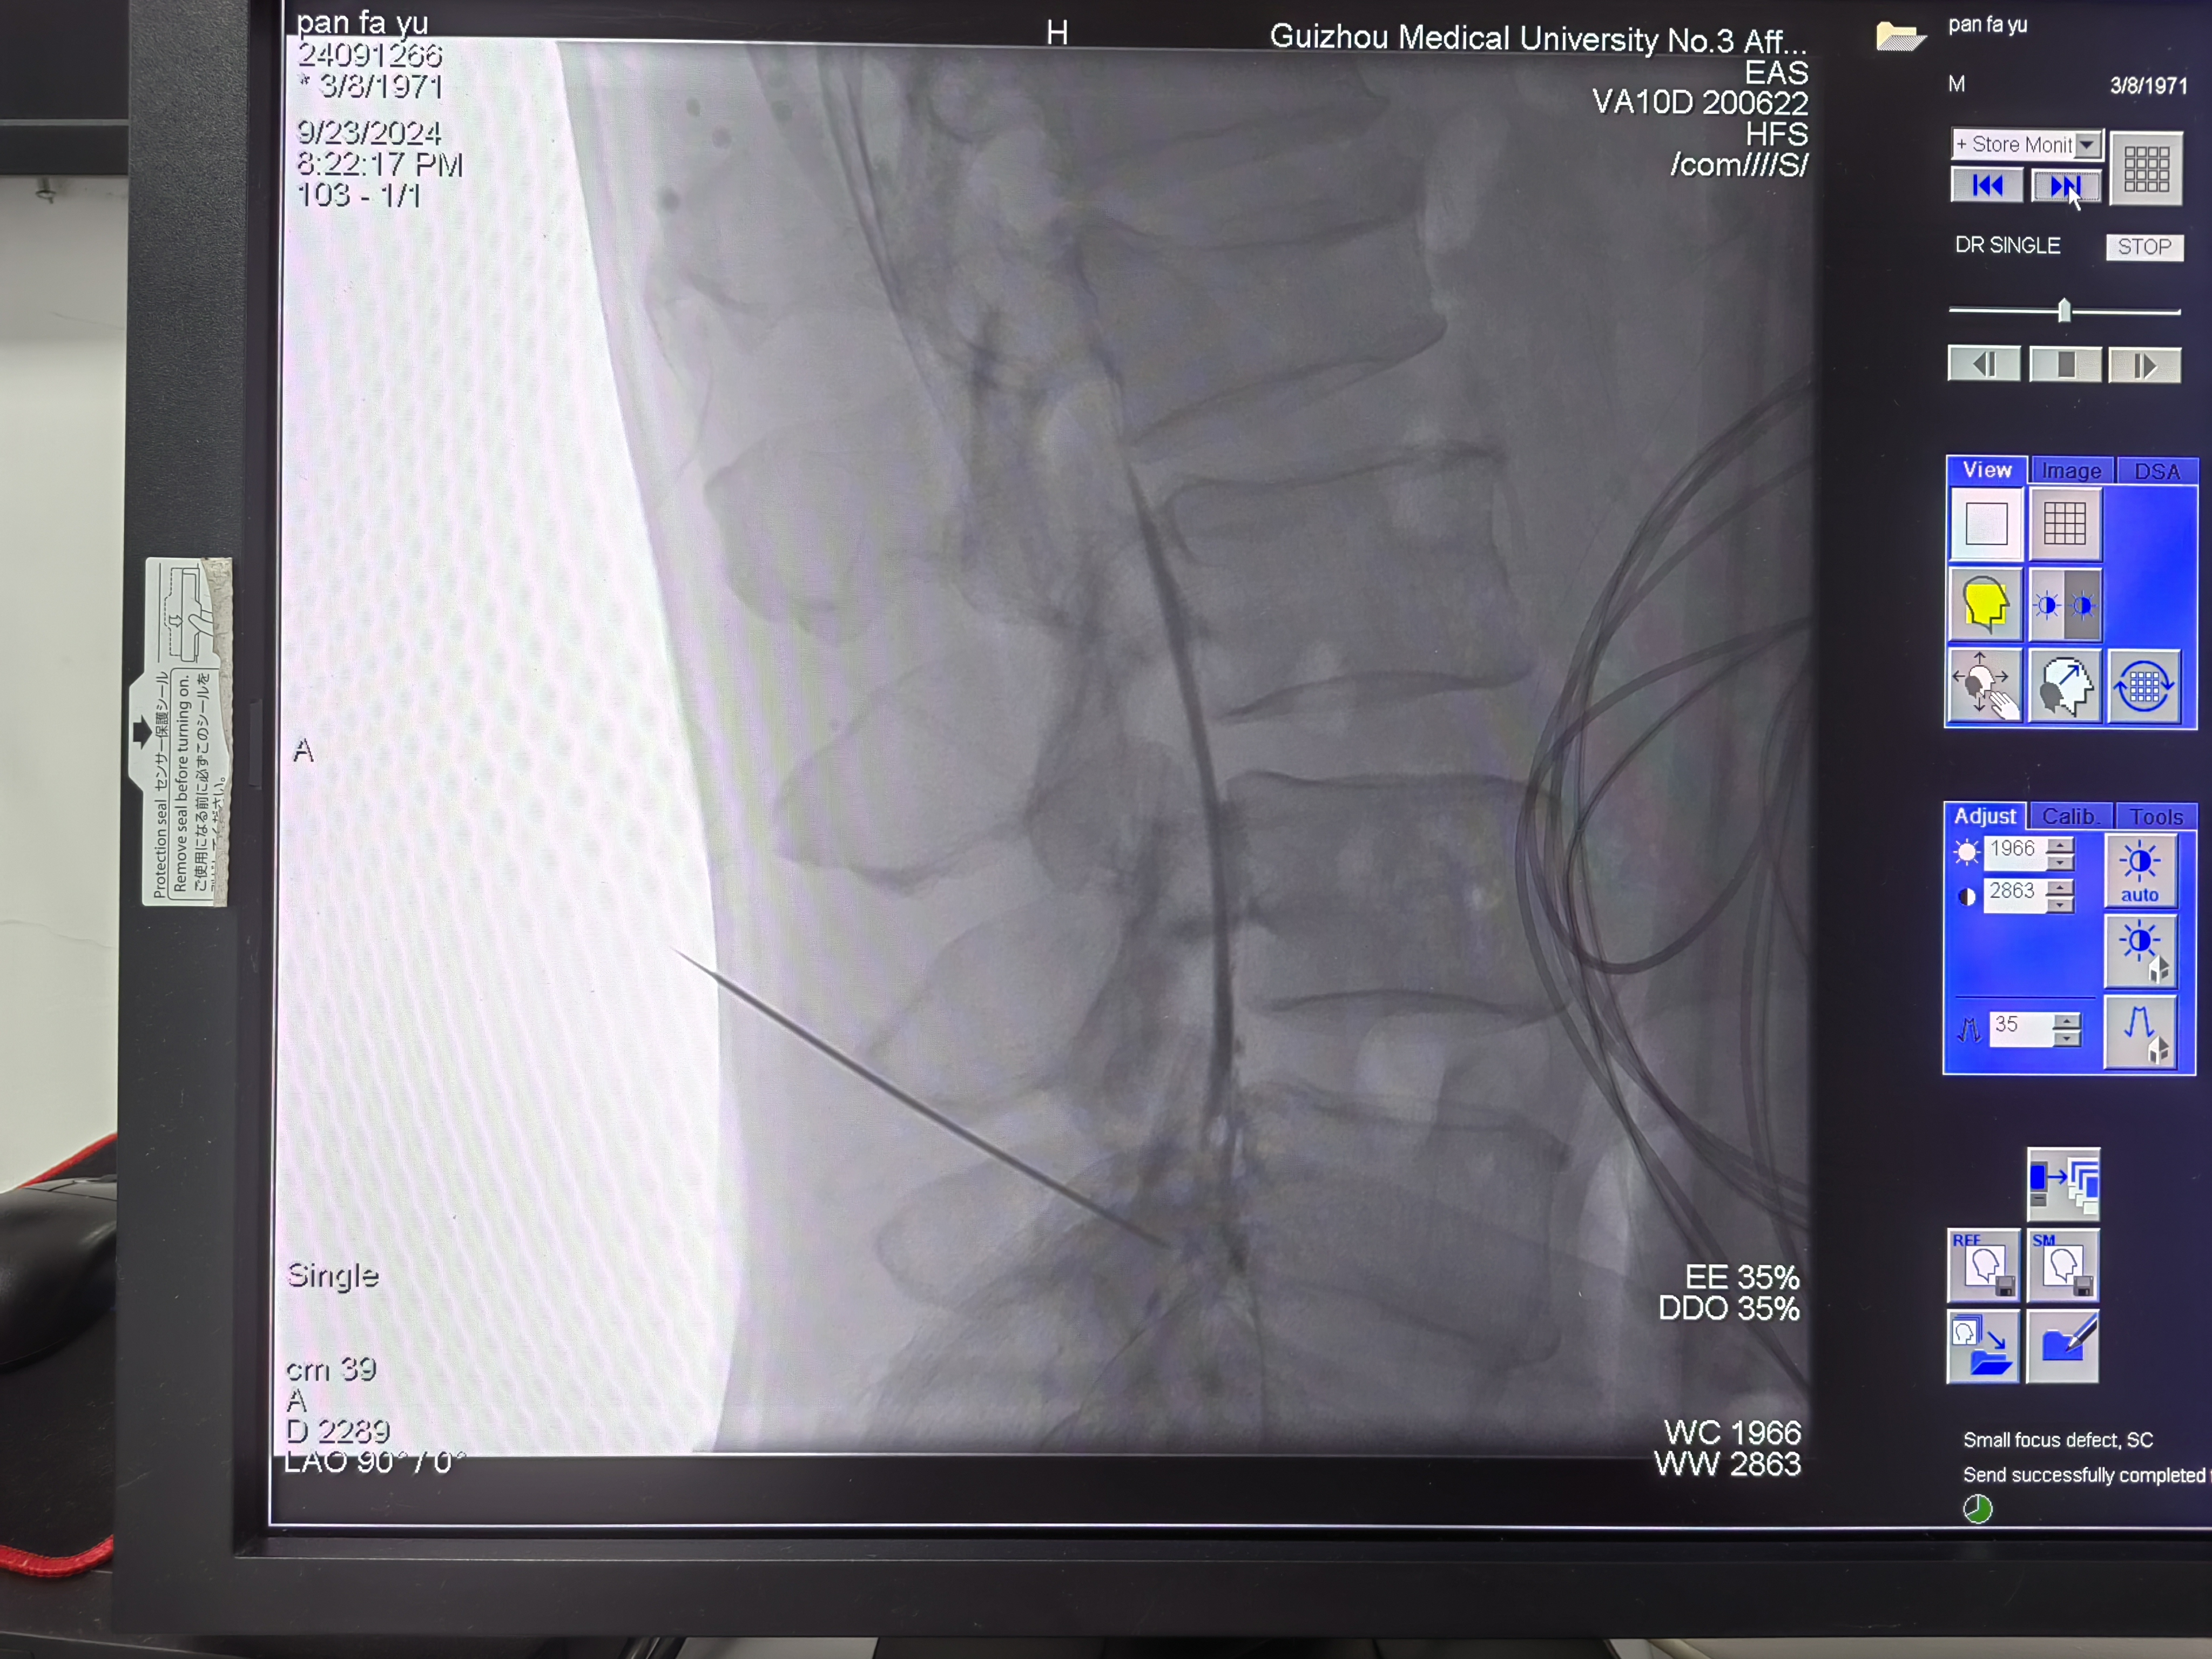

腰椎C臂透视下